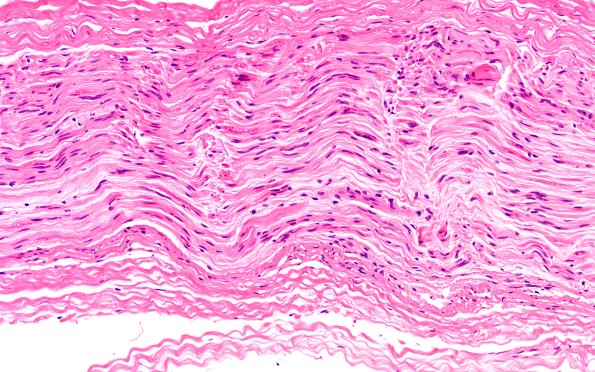

4A3 (Case 4) H&E 20X 1

In this longitudinal section a fascicle shows focal pallor. (H&E)